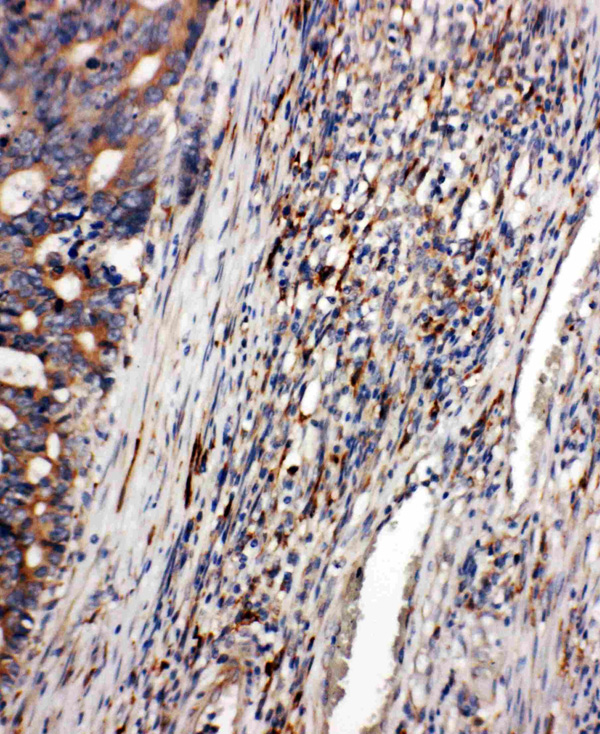

IHC (Immunohiostchemistry)

(Anti-CD163 antibody, AAA45367, IHC(P)IHC(P): Human Intestinal Cancer Tissue)